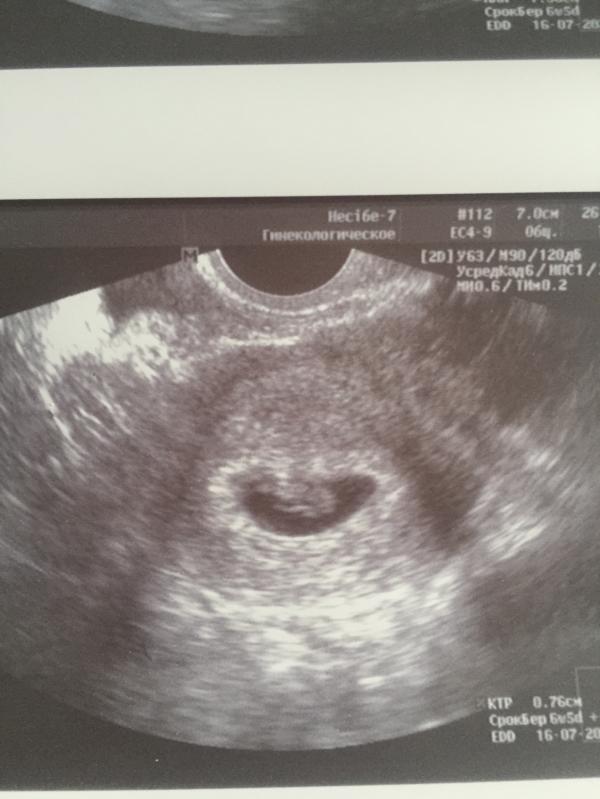

Наша первая фотография😍! Боже, как же это круто слышать сердечко своей крохи👼🏻🥰! Нам сегодня 6 неделек и 5 дней🤰🏼! Наш маленький ангелочек мы с папой тебя очень любим🥰!

Вообще 7 недель и 4 дня акушерских по последней менструации! А по узи вчера показало 6 недель 5 дней